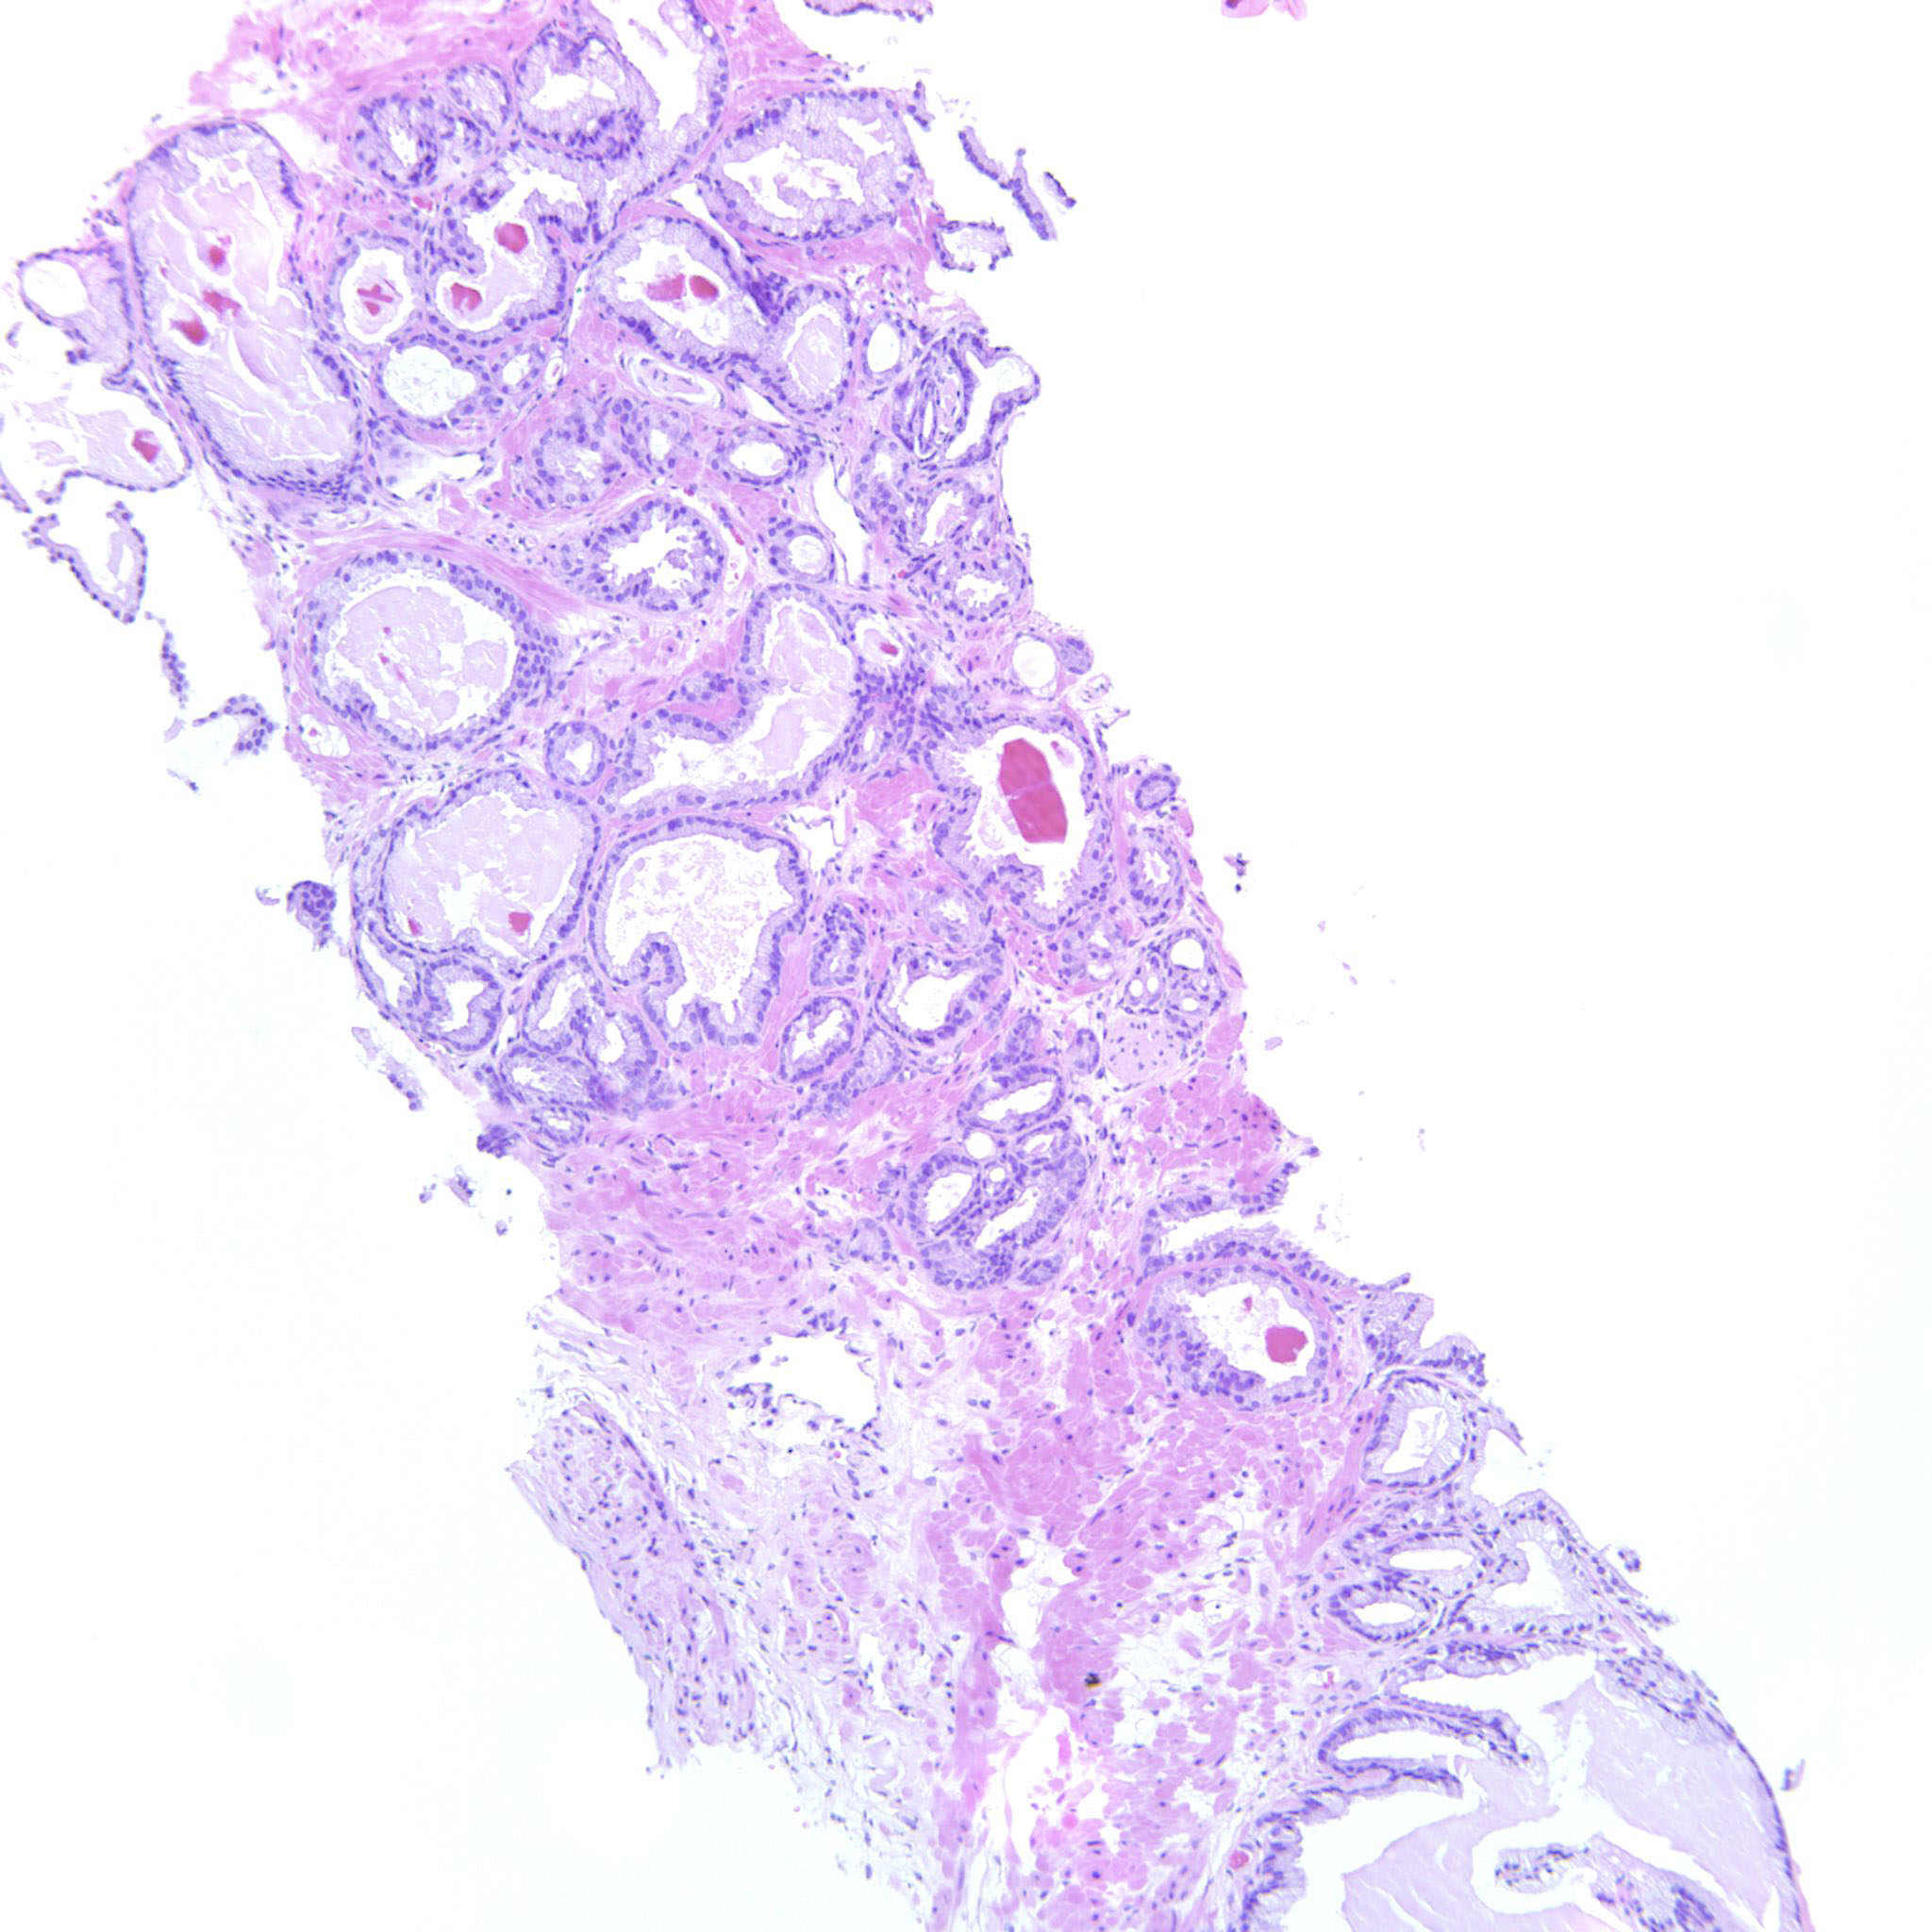

Consensus grade: GS 3+3=6 (ISUP 1)

3+3=6 with an occasional seemingly fused gland that may be a tangential cut.